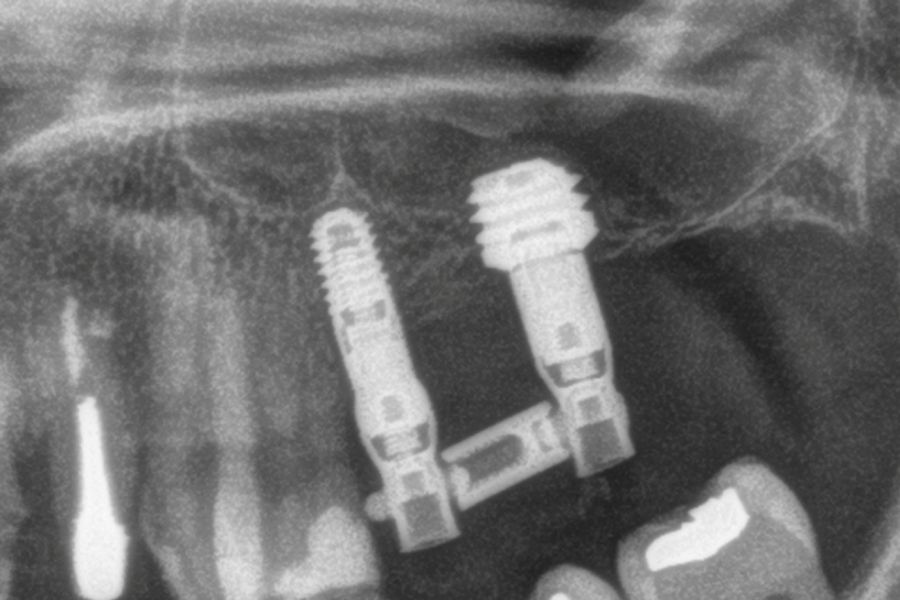

Para estimar la pérdida ósea marginal, se utilizó una referencia de longitud conocida en las radiografías, específicamente la longitud del implante, con el fin de calibrar las mediciones obtenidas. A partir de esta calibración, el software empleado (Digora for Windows, SOREDEX Digital Imaging Systems) calculó las mediciones reales. La pérdida ósea crestal marginal se determinó midiendo la distancia desde el hombro del implante hasta el primer punto donde se evidenció contacto óseo con el implante. Para evaluar la evolución de la reabsorción ósea en cada paciente, se utilizó como referencia la radiografía tomada en el momento de la colocación de la prótesis. Posteriormente, los pacientes asistieron a controles periódicos cada seis meses, en los cuales se realizaron nuevas radiografías de seguimiento. Durante las visitas postoperatorias y tras la colocación de la prótesis, se registraron en la historia clínica cualquier posible complicación protésica o quirúrgica, las cuales fueron posteriormente analizadas.

La media de seguimiento de los implantes estudiados fue de 36,3 meses (+/- 2,71); rango 36-42 meses y durante este tiempo no se produjo ningún fracaso, siendo la supervivencia acumulada del 100%. La media de la pérdida ósea mesial al final del seguimiento para todos los implantes fue de 0,35 mm (+/- 0,62) mientras que la distal fue de 0,11 mm (/- 0,49).

En las Figuras 7- 13 se muestra uno de los casos incluidos en el estudio.